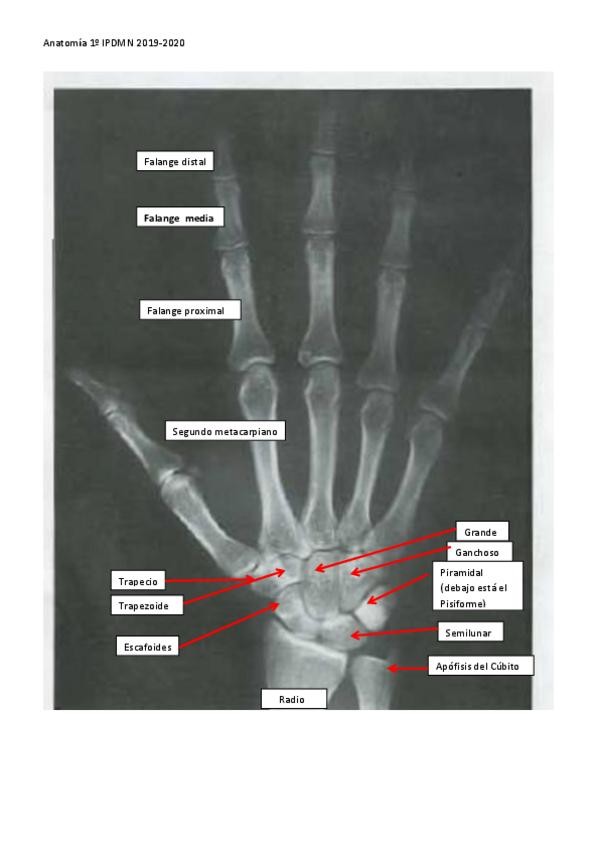

INGENIERO DE LA CIERVA - Imagen para el Diagnóstico y Medicina Nuclear

Anatomía por la imagen